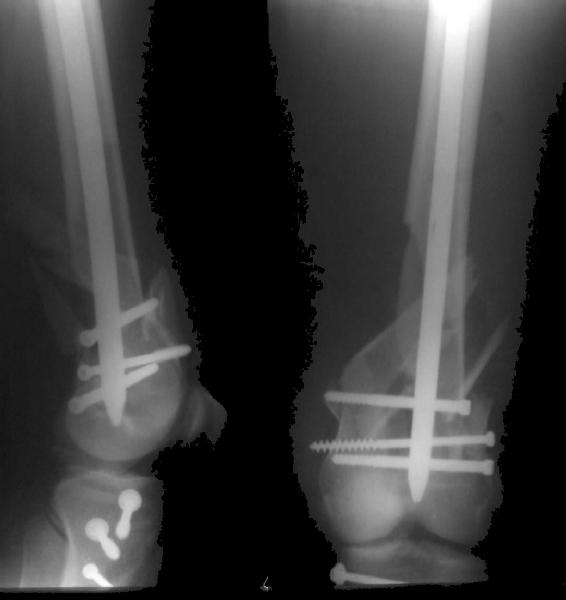

And why LISS is superior here than nail?

Look what we would have done.

I would not say that the LISS is superior to the nail. If I would, I had not post original mail. I wanted to generate discussion. Your option is a very viable one. I feel a little bit shaky the distal femur, but it is just gut feeling no science behind it. Any way nice fixation, congarts!